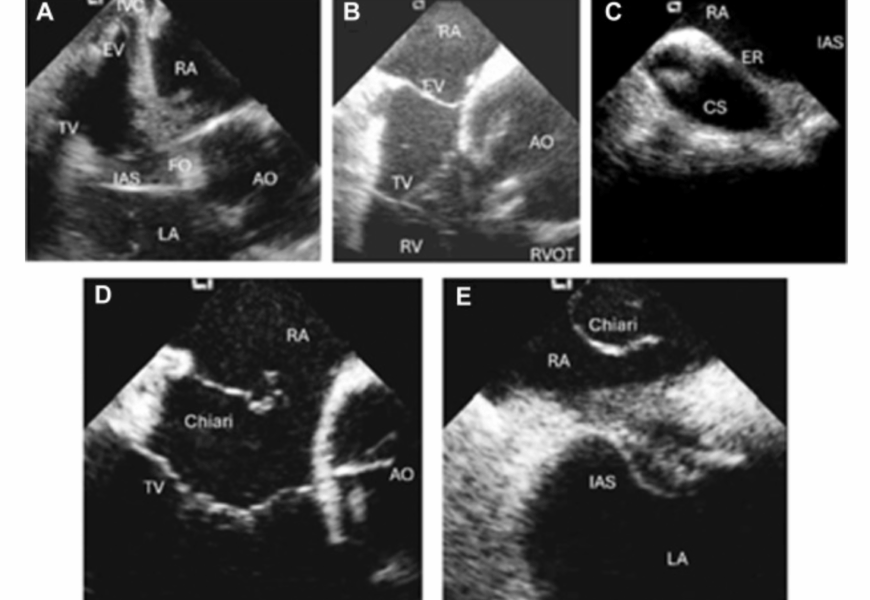

L’ecocardiografia intracardiaca (ICE) è una tecnica di imaging minimamente invasiva che offre visualizzazioni in tempo reale e ad alta risoluzione delle strutture cardiache, eliminando la necessità di anestesia generale.

Vengono forniti protocolli standardizzati per interventi sulle valvole mitrale, tricuspide, polmonare, chiusura dell’auricola sinistra e difetti del setto interatriale.